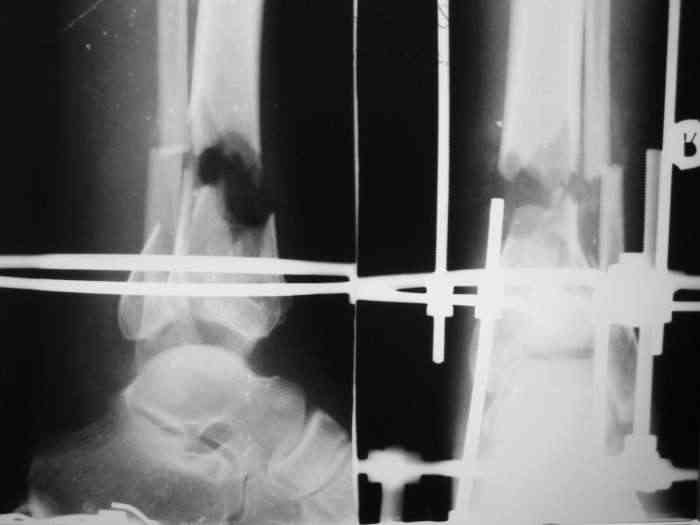

Re: Открытый вн.суставной перелом голени

Состояние раны: постепенно очищается, заполняется грануляциями с участками фибрина. Воспаление мягких тканей вокруг раны купировано. В глубине раны, ближе к дистальному отломку, остается небольшой "гнилой угол" с весьма скудным отделяемым. Две "большие" перевязки в течение недели, с частичными некр- и секвестрэктомиями в условиях операционной.

При закрытой попытке поймать и собрать отломки дистального фрагмента спицами с напайками, удача покинула меня.:-(

Срепонировать суставную поверхность мне не удалось. Только зря прошил ткани, а отломки остались в прежней позиции. Так и подмывало провести спицу через ахилл ... или пойти открыто задним доступом и притянуть винтом. Но смущает один момент: на чем будет держаться резьбовая часть винта, если передная поверхность разбита в хлам? Винт будеть елозить и не даст должной копрессии. Есть ли резон, при нынешнем состоянии раны, пойти на открытую репозицию заднего отдела суставной поверхности?